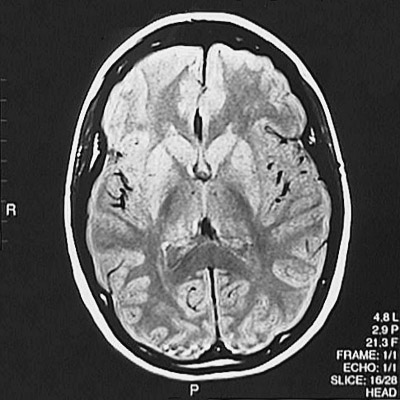

This is a normal axial proton density MRI scan demonstrating the frontal lobe and parietal lobe and occipital lobe and splenium of corpus callosum and caudate and putamen and globus pallidus and thalamus and internal capsule.